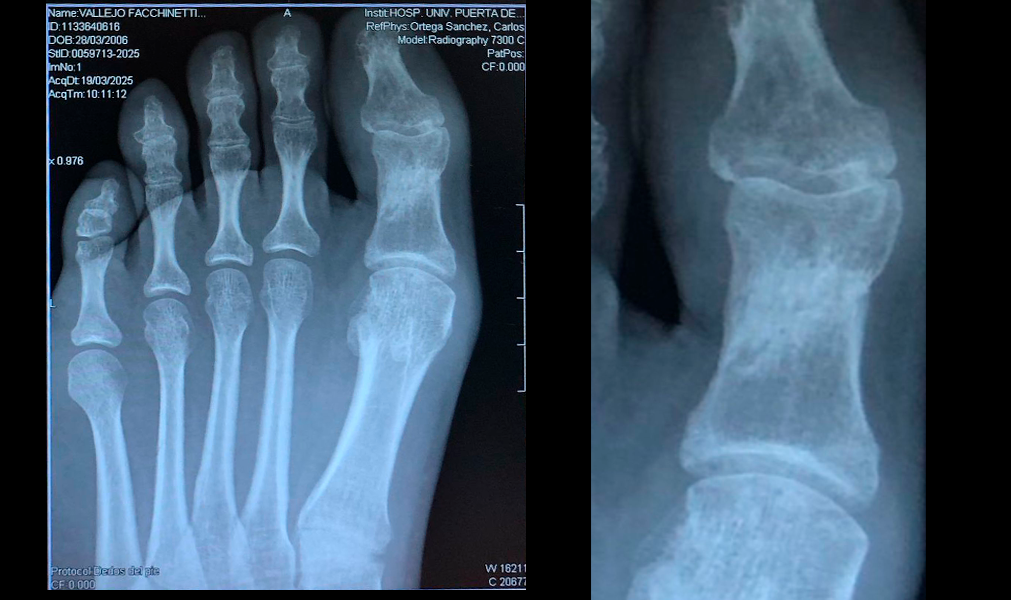

Tratamiento

- Se le aplican tres sesiones de bomba diamagnética

Protocolos de terapia diamagnética

- Movilización de líquidos Extra H/ Intra H 10´

- Membrana celular 5´

- Bioestimulación: Hueso cartílago 10´

Evolución

Después de la tercera sesión el paciente no manifiesta dolor y se aprecia claramente en la imagen la evolución en la consolidación de la fractura.